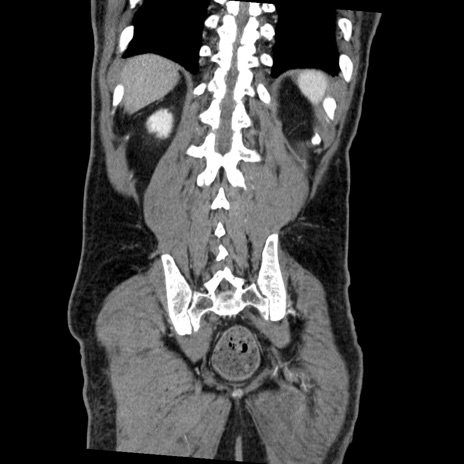

症例22(冠状断像)

【症例】50歳代男性

【主訴】腹痛

【現病歴】AVMからの被殻出血のため回復期リハ病棟入院中。 本日午後3時頃急に下腹部痛が出現した。

【既往歴】AVM、被殻出血、虫垂炎、高血圧

【身体所見】意識晴明、左半身不全麻痺、会話の理解は良好、36.5°C、腹部:膨隆、全体に板状硬、下腹部正中に圧痛点あり、反跳痛-、筋性防御不明、右下腹部にope scar

【データ】WBC 9400、CRP 0.06